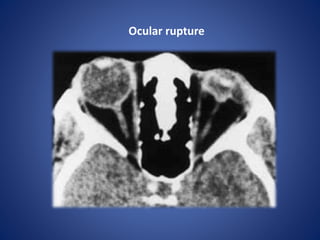

Ocular rupture

• #5 Ocular rupture. Axial CT scan shows deformity of the left eye with uveoscleral infolding due to ocular hypotony related to a rupture.